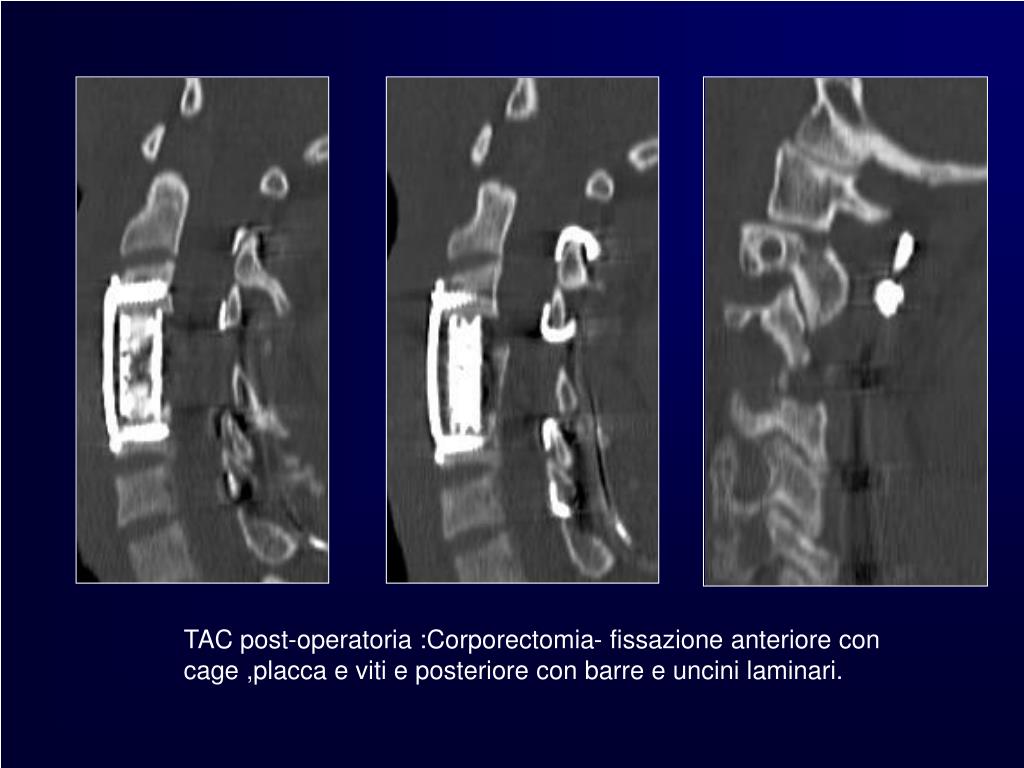

9. TAC post-operatoria : Corporectomia - fissazione anteriore con cage ,placca e viti e posteriore con barre e uncini laminari.

12. TAC post-operatoria :Corporectomia- fissazione anteriore con cage ,placca e viti e posteriore con barre e uncini laminari.